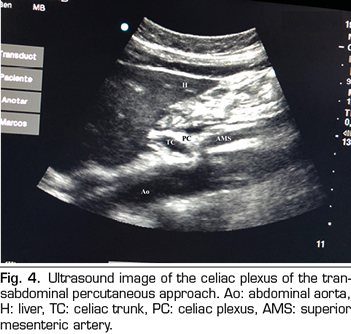

In recent years, ultrasound has made head against fluoroscopy and CT in interventional pain management. The first describing the technique on the celiac plexus was Bhatnagar (31), and it could be performed percutaneously at the patient’s bedside and supine, which gives greater comfort for both the patient and the doctor. However, there are still no randomized controlled trials comparing abdominal ultrasound neurolysis of the celiac plexus versus opioid systemic treatment. The technique is performed using a convex transducer (2-5 MHz), initially placed just below the xiphoid process in the transverse plane, to identify structures, such as liver, stomach, intestine, portal veins, cava and aorta. With the help of the Doppler, we scanned caudally to identify the bifurcation of the celiac trunk in the hepatic and splenic arteries, and more distally in the superior mesenteric artery. Then we rotate the transducer in the longitudinal plane, visualizing in the same image the bifurcation of the aorta in the celiac trunk and in the superior mesenteric artery with the celiac plexus surrounding these structures. The approach is performed in plane, transabdominal, through the liver or stomach, as long as there are no large vessels interfering with the needle path (Figure 4).